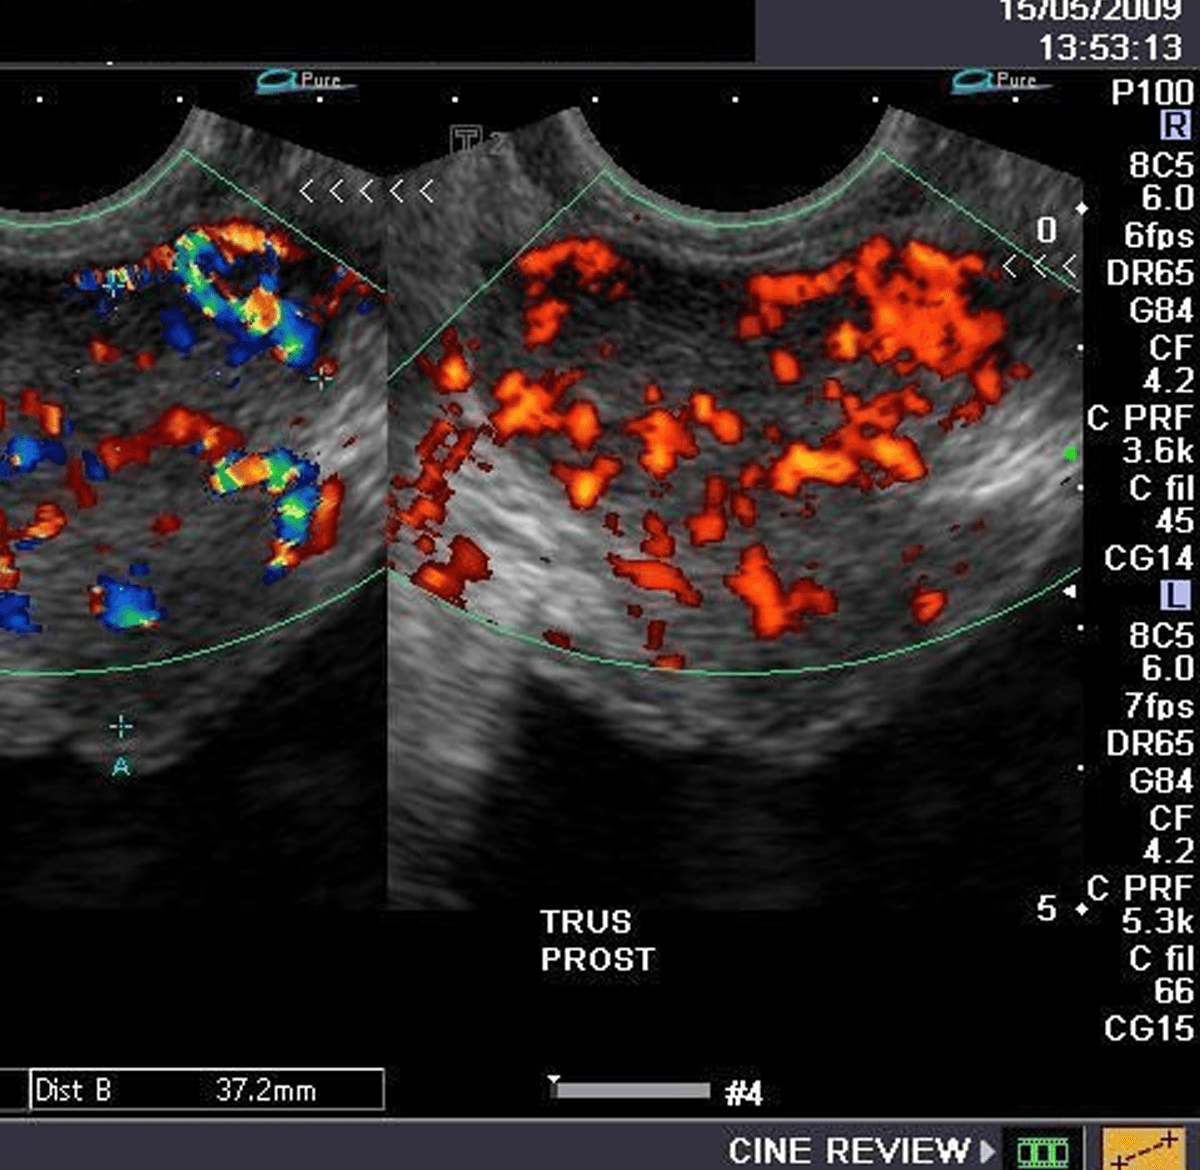

An incredibly powerful tool that finds applications in the fields of vascular and musculoskeletal imaging. Our high-end Philips, GE and Mindray systems present in our centers provide the most accurate results.